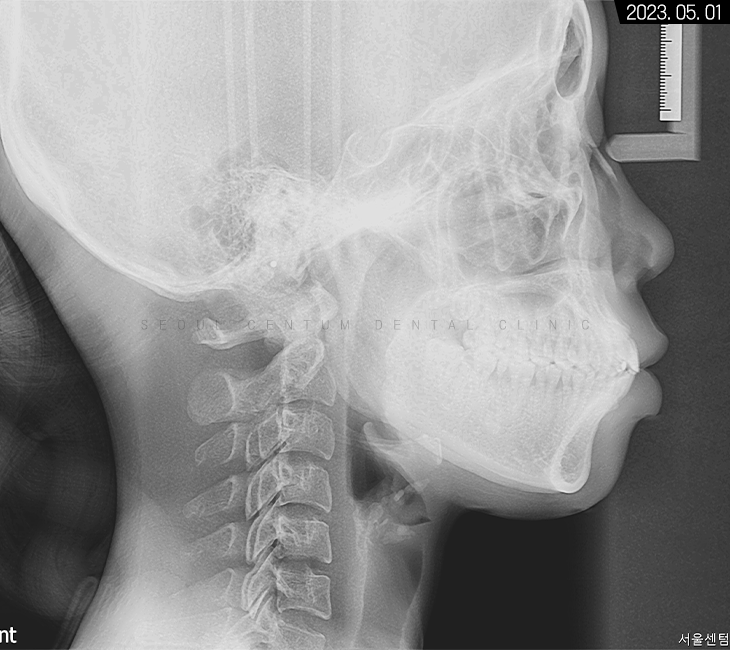

세팔로 측면 사진을 보면

확실히 수평피개 상태가 눈에 띄고

코끝부터 턱 끝까지 심미선을 그었을 때

입술이 과하게 넘어간 것을 볼 수 있었는데요.

입이 튀어나와서

아래턱이 들어간 양상도 보이지만

치아 전돌을 해소하면

아래턱이 자연스럽게 전상방으로 올라와서

구조적으로 정상 범주에 돌아오게 됩니다.

치조골 상태는 양호해서

치근 이동에 무리가 없을 것으로 예상됐고요.